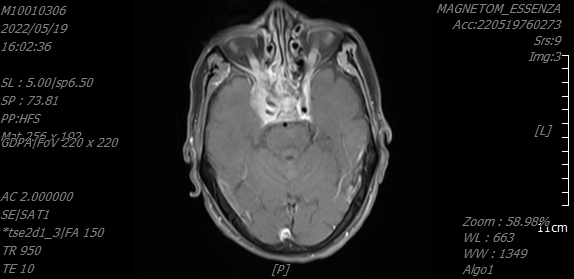

鼻咽癌治療前VS鼻咽癌治療后

60歲的林先生因反復鼻出血半年有余,且伴有雙側(cè)眼球活動障礙,診斷系鼻咽癌。之前一直在其他醫(yī)院治療,聽說我院與國科大腫瘤醫(yī)院締結(jié)院間協(xié)作,每周有國家級腫瘤專家坐診,遂轉(zhuǎn)診我院。入院后,在國科大腫瘤醫(yī)院頭頸放療專家花永虹教授的精心治療下,目前,林先生眼球已恢復正常運動功能,取得較好的治療效果,有效提高了生活質(zhì)量。